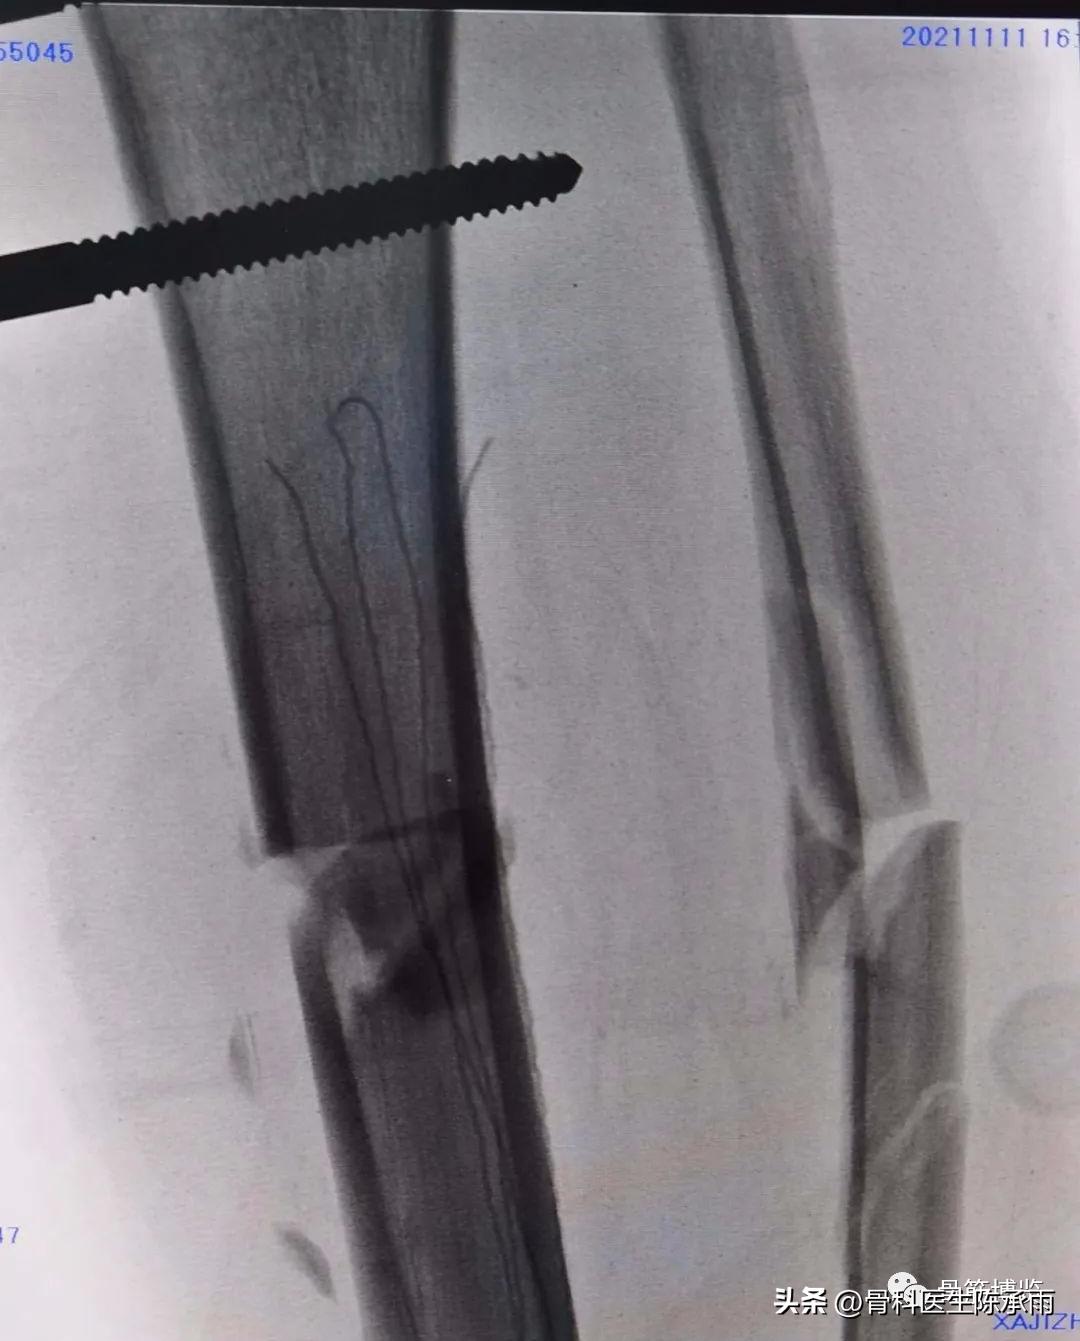

这是1例开放性胫腓骨多段骨折患者,胫骨远端pilo骨折(pilon骨折指累及胫距关节面的胫骨远端骨折,通常是指胫骨远端三分之一,波及胫距关节面的骨折,胫骨远端关节面严重粉碎,会出现骨质的缺失以及的远端松质植骨的压缩,并常合并有的腿骨下端的骨折以及严重的软组织挫伤。)

胫骨中段开放性骨折,一期行清创骨牵引,二期见骨创口愈合差,行远端骨折切开复位内固定,中段骨折行外固定架固定,必要时3月后视情况可改内固定。

术中C臂